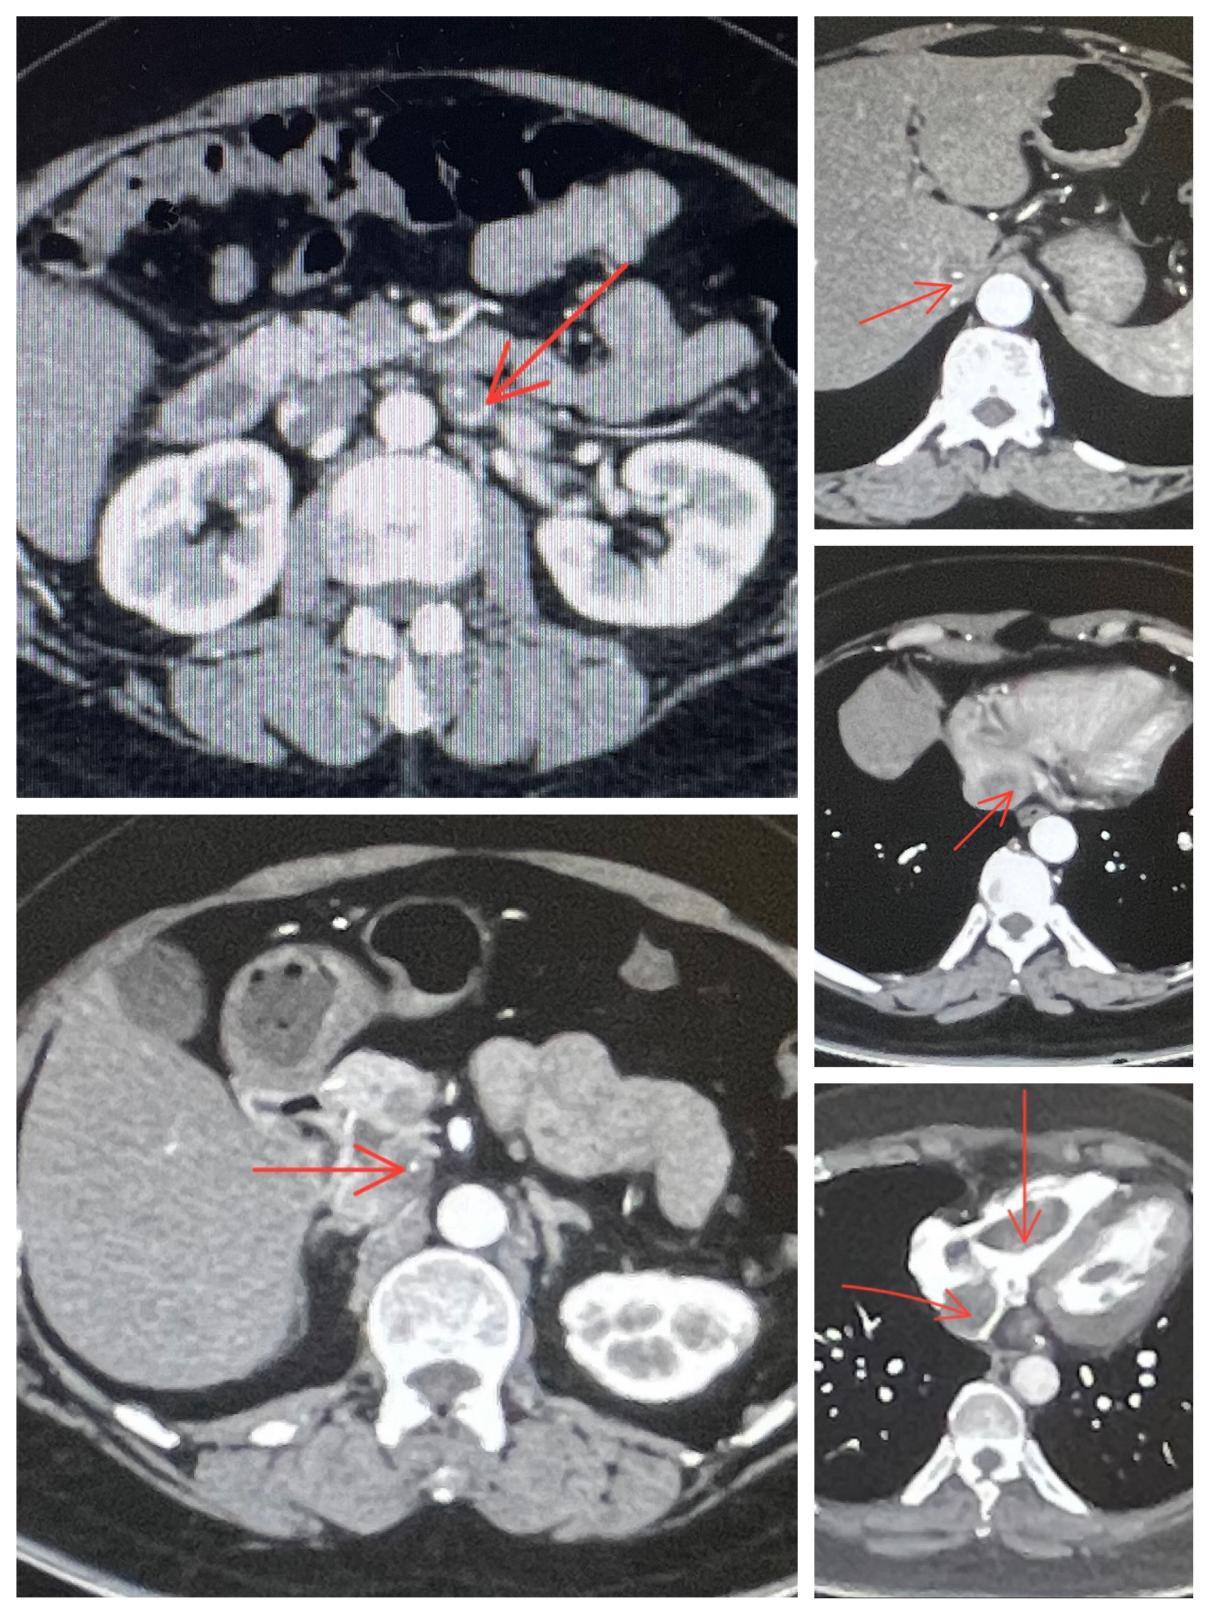

患者在我院入院后,心脏外科吴向阳主任团队继续完善静脉系统CTA、头颅CT、妇科超声等相关检查。经查其CTA显示:子宫多发肌瘤,并沿左侧卵巢静脉向上延伸至左侧肾静脉-下腔静脉-右房右室,卵巢动脉发出供血血管,双肺动脉未见栓子,头颅未见明显异常;超声检查(子宫、附件经腹壁)显示:子宫肌瘤(多发),并沿左侧卵巢静脉向上延伸,双侧附件未见明显异常。结合患者既往病史,明确诊断其为静脉内平滑肌瘤(IVL)。

术前影像资料